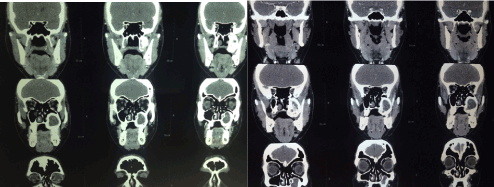

Paranasal sinus CT scan revealedthat the lesion was originating from the inferior wall of the maxillary sinus and was surrounding the left posterior molar teeth. The central part of the lesion had soft tissue dansity, periferal areas had ground glass opacity and the nature of the lesion was expansile (Figure 1). Age and radiological findings of the patient were compatible with the fibrous dysplasia.

Figure 1. Expansile lesion was originating from the inferior wall of the maxillary sinus. Central soft tissue dansity and peripheral ground glass opacity can be seen.